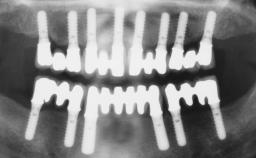

Conventional Loading of Eight Implants in the Maxilla and Final Restoration with a Full-Arch Gold-Ceramic FDP

A 35-year-old Caucasian female presenting with advanced periodontal disease involving both the maxillary and the mandibular dentition was referred for evaluation. The patient, a non-smoker in good general health, requested treatment for recurrent periodontal abscesses, tooth mobility, and discomfort during chewing, as well as restoration of her missing teeth with a fixed prosthesis to improve mastication and esthetics. All residual maxillary teeth exhibited plaque deposits, deep pockets, bleeding on probing, and class III mobility and were evaluated as hopeless. All residual mandibular teeth except tooth 37 could be maintained after periodontal therapy.

# of Implants 8

Type of Implants One-Piece

Defining Characteristics Fully edentulous upper jaw to be rehabilitated with four or more implants